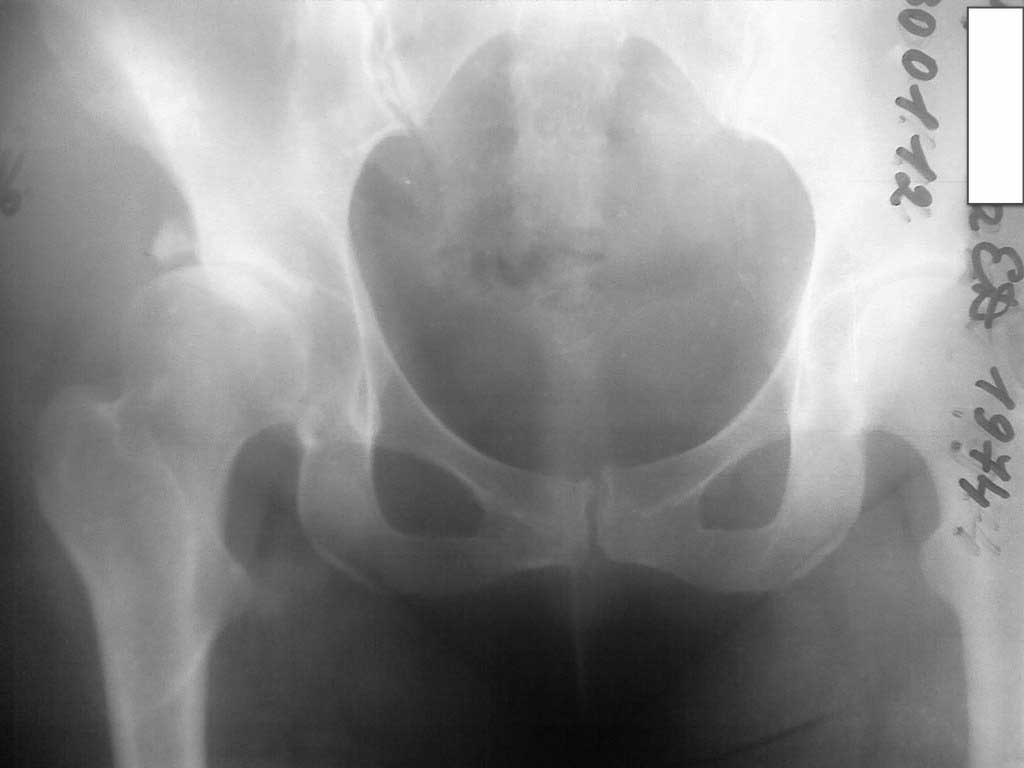

Дорогие коллеги! Прошу помочь медработнику, прежде всего тактикой лечения. Женщина, медсестра отделения городской больницы хирургического профиля, 35лет, после родов 4 года назад стала отмечать боли в правом тазобедренном суставе. Ходит едва прихрамывая, хотя сама замечает, что хромает достаточно сильно.Были выполнены снимки, через 2 года РКТ(2010). На сегодня на рентгенограмме (в приложении) тазобедренного сустава свободный фрагмент крыши вертлужной впадины, сужение латеральной трети суставной щели. Травму категорически отрицает. Судить сегодня - что это - незамеченный перелом или вариант дисплазии трудно и с точки зрения здоровья сустава - бессмысленно. Вопросы следующие: 1. Можно ли сохранить сустав? 2. если да, объем операции? 3. кто возьмется? 4. если нет смысла сохранять, т.е. невозможно, какой вариант протезирования оптимален?

На снимках тяжело оценить, но складывается впечатление, что суставной хрящ сохранен. Имеется подвывих кнаружи из-за перелома суставной части крыши вертлужной впадины. Я бы не исключил остеосинтез.

Здесь явная дисплазия с стрессовым переломом латерального края вертлужной впадины. Генез стрессовых переломов за счет нагрузки головкой в латеральный край, где сперва образуется зона разрежения, затем образование кисты в толще кости. Продолжающиеся нагрузки приводят

к стрессу, и истонченные стенки не выдерживают, что приводит к перелому.

При рентген картине СЕ (Center Edge) меньше 5 градусов и вальгус около 142 градусов, а также молодой возраст является прямым показанием для Периацетабулярной Остеотомии и Варусной остеотомии.

Для расчета остеотомии необходимы качественные снимки прямого таза и боковой снимок. Установка бокового снимка описана в прежних дискуссиях. Прямой снимок дает ответы о состоянии хряща, а артроскопия для ПАО является малоинформативным исследованием. А имеющиеся

небольшие повреждения хряща восстановится при изменении остетотомией геометрии нагрузки.